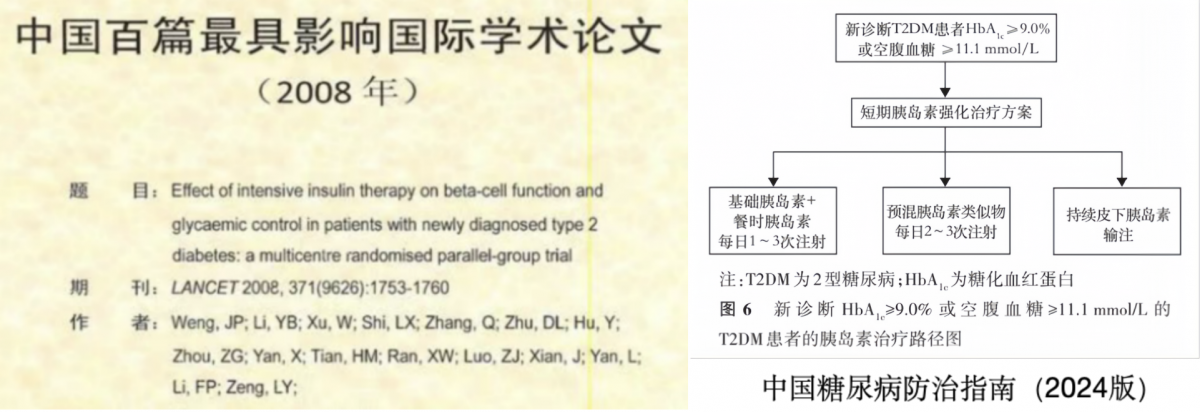

★2型糖尿病强化治疗

针对新诊断2型糖尿病患者,率先建立并推广以“胰岛β细胞休整”为核心的早期胰岛素强化治疗新方案。该方案被《中国2型糖尿病防治指南》采纳,相关适应症与疗程的专家共识更推向国际,为全球糖尿病治疗提供了“中国方案”。

学科团队持续开展研究,明确了各类治疗方案在中国人群中的有效性与安全性,为临床指南的制定与更新贡献了核心循证依据。